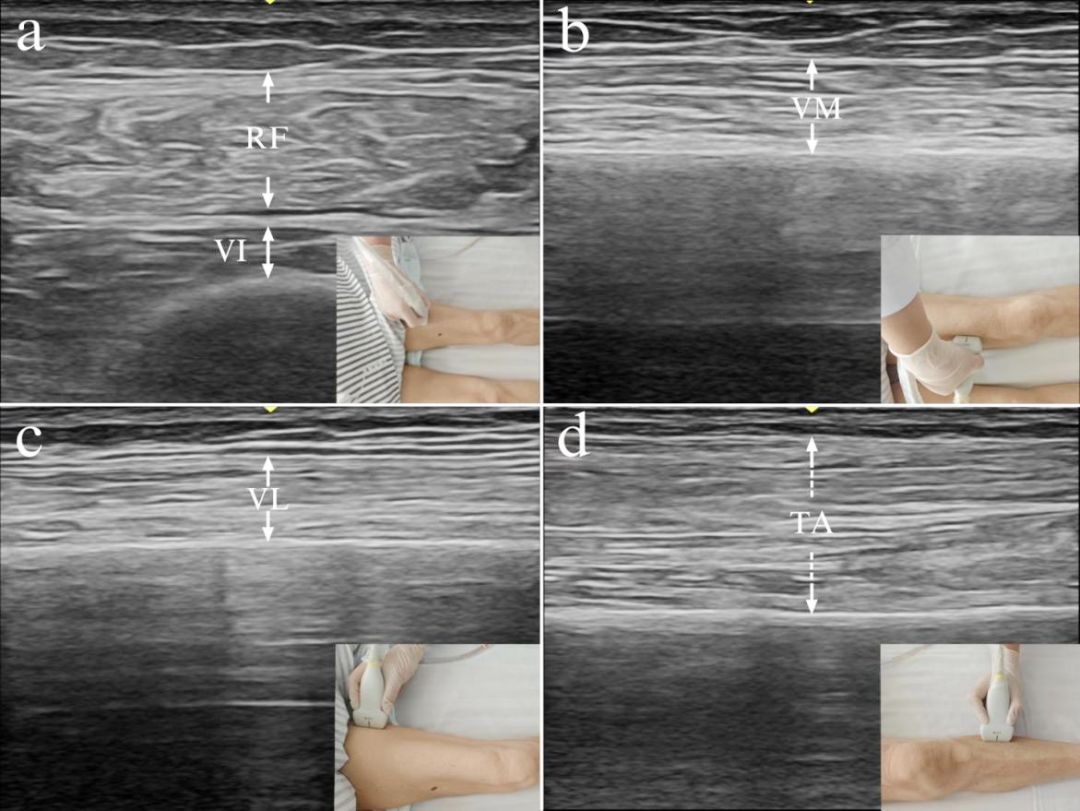

为破解这一临床痛点,研究团队创新性采用患者自身对照设计,在常规康复基础上引入悬吊式下肢康复机器人。通过个体化参数设置与多关节协同训练,并借助肌骨超声等客观评估手段,团队系统观察了该技术对患者下肢肌肉厚度、肌力及关节活动度的短期改善效果。值得一提的是,这款悬吊式下肢康复机器人正是由方凡夫教授前期牵头上海市“科技创新行动计划”生物医药领域科技支撑项目、上海市申康医企融合创新成果转化专项等研发而成的医工结合成果。

肌骨超声评估肌肉状况

数据显示:干预侧肌肉厚度仅下降0.2%,远低于对照组的6.3%;MRC肌力评分及髋膝关节主动活动度也显著优于单纯常规康复组。尤其在老年患者和正常BMI患者中,获益更为突出。同时,设备表现出良好的安全性,无相关不良事件发生,患者满意度达95%。